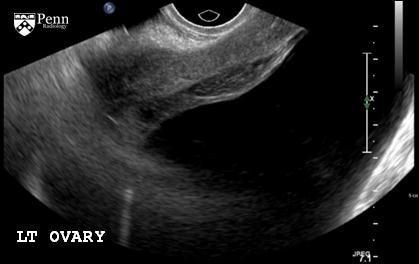

Peritoneal inclusion cyst

Imaging features

Ovary may lie in center of cyst, suspended by thin adhesions, like a spider in a web.

Ovary may be eccentrically located within the cyst, adherent to the cyst wall.

Ovary may lie within the cyst wall.

Adjacent ovary will be normal in appearance, though may be slightly distorted due to mass effect.

No enhancing components will be identified on contrast-enhanced CT or MRI; the adjacent normal ovary should not be confused with a mural nodule.

Low-resistance flow may be detected in septations on Doppler flow ultrasonography due to small vessels traversing the mesothelial tissue in the cyst walls.